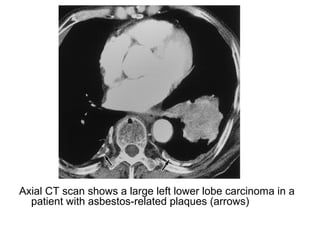

Axial CT scan shows a large left lower lobe carcinoma in a

patient with asbestos-related plaques (arrows)